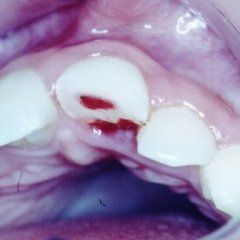

P3: Il trattamento endodontico si rende necessario quando la polpa del dente, comunemente chiamata dai Pazienti “nervo” è stata irrimediabilmente danneggiata da carie penetranti, fratture dentali, traumi o da cause imputabili a pratiche odontoiatriche scorrette. A volte la devitalizzazione del dente si rende necessaria, in corso di riabilitazioni protesiche complesse, per prevenire possibili problemi di ipersensibilità o per poter coinvolgere nel progetto terapeutico di recupero denti già di per se compromessi dal punto di vista parodontale. Presupposto per ottenere il successo in tale terapia è l’applicazione di un serio protocollo operativo che prevede tra l’altro l’uso di un telo di lattice, chiamato comunemente “diga”, che consenta la detersione e la pulizia dei canali del dente in un ambiente sterile e il controllo delle diverse fasi del trattamento attraverso delle radiografie endorali.